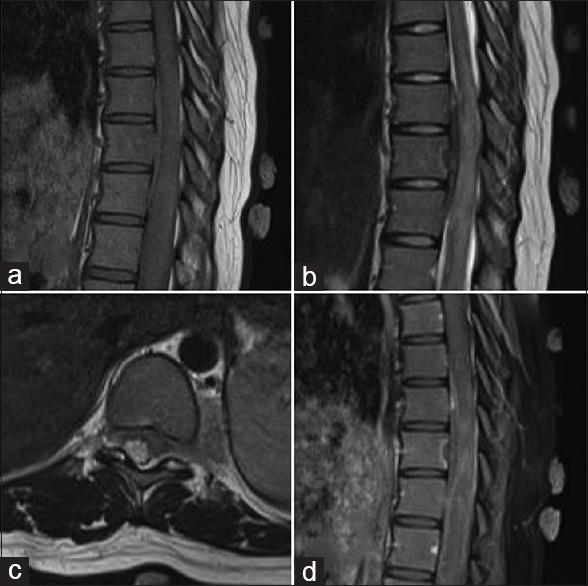

一例罕见的哑铃形原发性脊髓内周围原始神经外胚层肿瘤累及胸段脊髓硬膜外间隙

A Rare Case of Dumbbell-shaped Primary Intraspinal Peripheral Primitive Neuroectodermal Tumor Involving Thoracic Spinal Epidural Space.

Primary intraspinal primitive neuroectodermal tumor (PNET) is a type of round cell malignant tumor which is reported only above 100 in literature. We report a case of epidural thoracic peripheral PNET, discuss its pathological features, radiology, and treatment options.

原发性脊髓内原始神经外胚层肿瘤(PNET)是一种圆形细胞恶性肿瘤,文献报道仅100余例。我们报告1例胸段硬膜外周围型PNET病例,并讨论其病理特征、影像学表现及治疗方案。